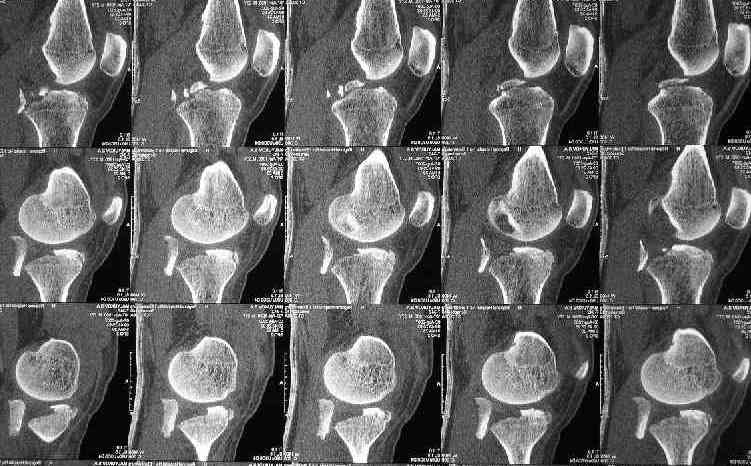

Для определения доступа сагитальные срезы менее информативны, необходимо иметь корональные срезы.

Корональные срезы дают информацию об апексе перелома, и также информацию о вовлечения суставной поверхности, что является немаловажным для прогноза.

Для фиксации переломов тибиал плато обычно применеяется техника создания buttress, пластинами с угловой стабильностью, но в данном случае эпифизарный фрагмент очень тонкий на всем протяжении и фиксировать такой перелом невозможно обычными традиционными методами фиксации.

Для лечения таких эпифизарных переломов применяется техника "создания исскуственного края тибиал плато".

Изгибаясь по контуру медиального эпифиза полу-или 1/3 тубулярные пластины создают медиальный край большеберцовой кости.

Радиально проведенные, через пластину и в эпихондральной зоне (пластина действует как шайба) тонкие 2.7 или 3.5 мм кортикальные шурупы до латерального кортекса создают адекватную фиксацию.

Операция из разряда травматологической "экзотики" прошла успешно. Доступ понравился:анатомичный, хорошая визуализация, удобно работать и оператору и ассистентам. Наложили пневможгут, но воспользовались им только на этапе ревизии сустава. Фрагмент развернулся на 90 град. на 2-ух "жгутах": медиально - сухожилие m.semitendinosus, латерально - задняя крестообразная связка. Мобилизовали,развернули и уложили на место без особого труда. Фиксировали отмоделированной 1/3-трубчатой пластиной. Мениск оказался неповрежден. Сустав стабилен. Обошлись без

иммобилизации, планируем начать ранние движения. Остальное на фото, дополнительно приложены корональные срезы КТ.